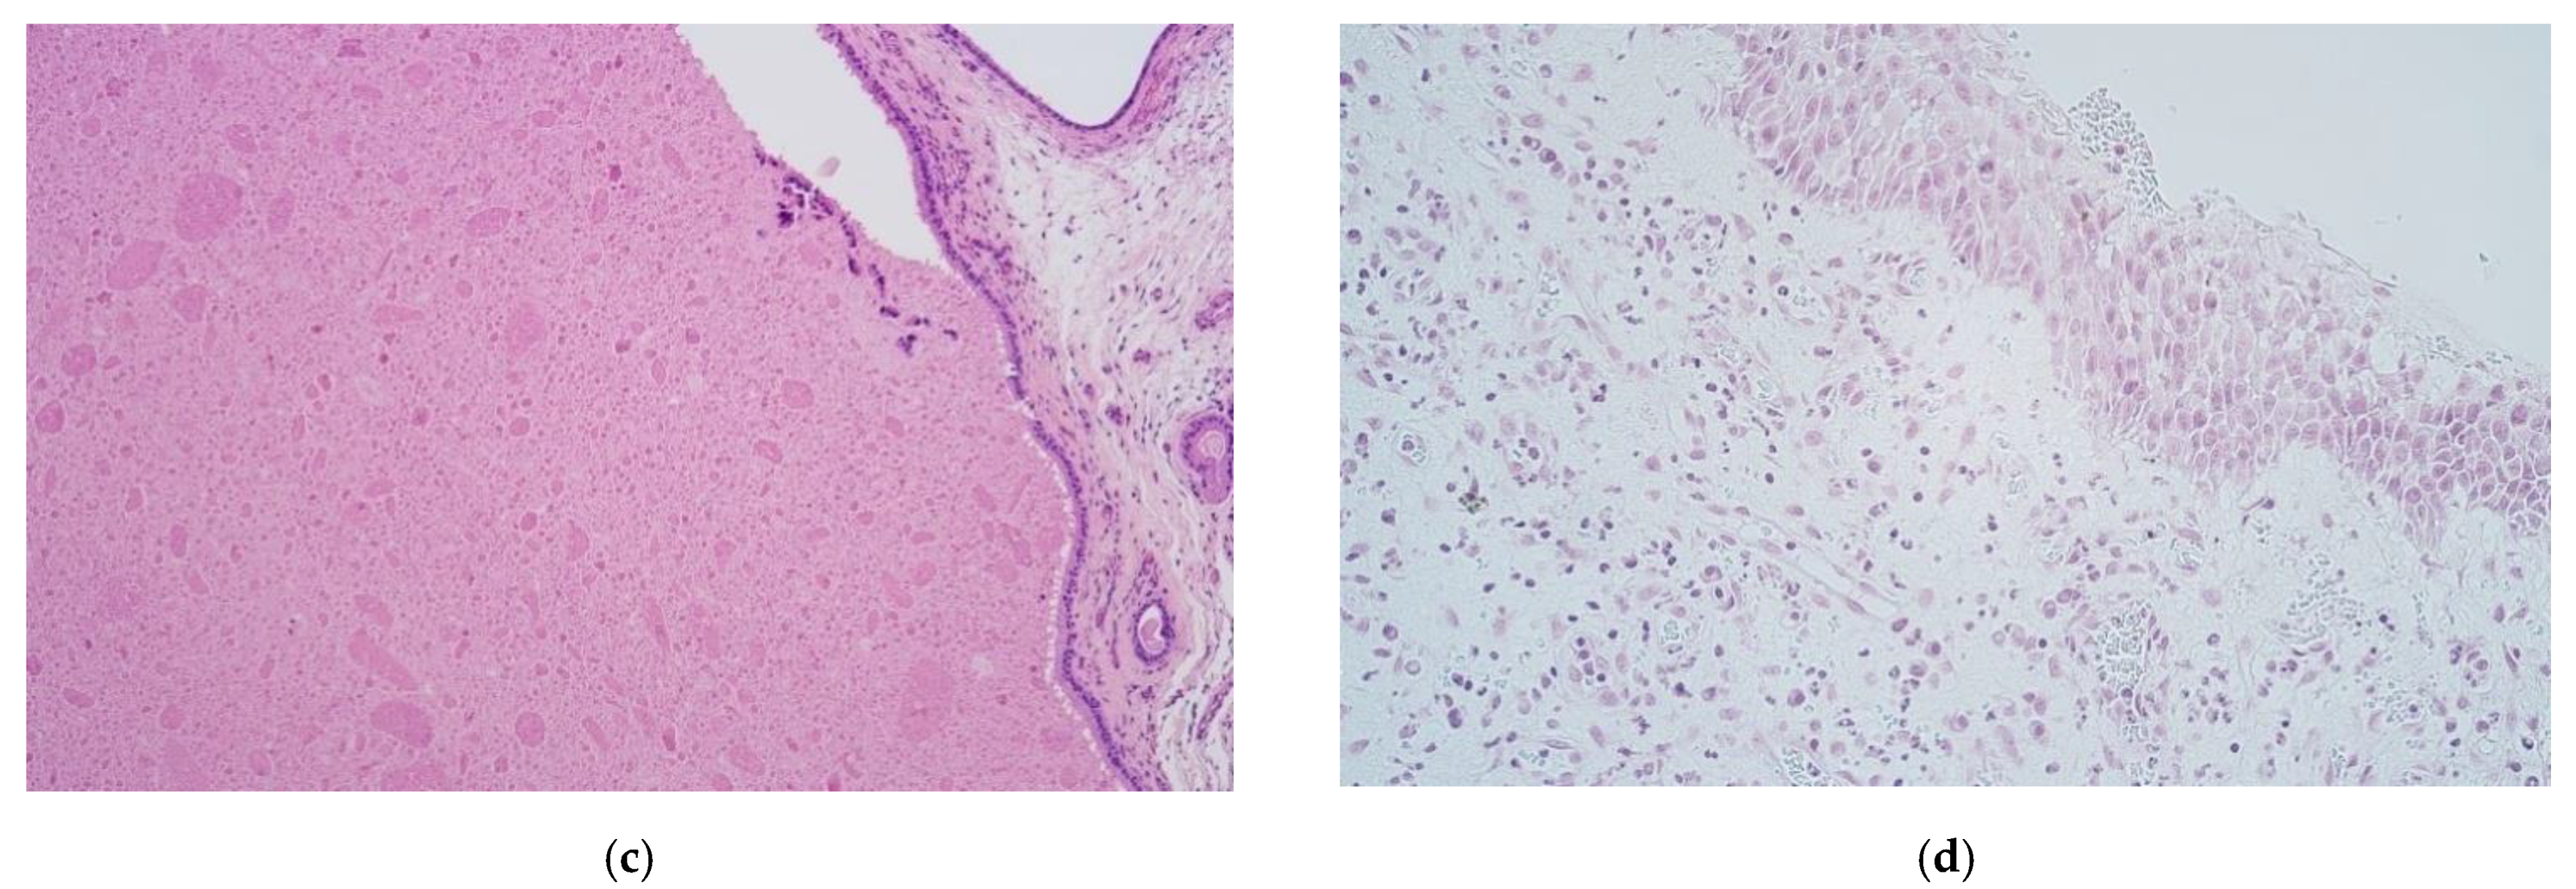

3. Results